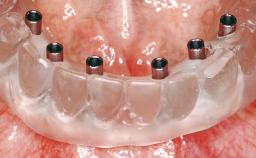

A 63-year-old female patient was referred to the University Medical Center in Groningen, Netherlands, for dental implant treatment. The patient had been edentulous in the upper jaw for 20 years. The remaining teeth in the lower jar had been removed two years before the consultation. The patient was wearing her first maxillary denture and her second mandibular denture; the latter was 1 year old at the time. The conventional upper denture had functioned satisfactorily for many years, but the patient complained about reduced stability and insufficient retention of her lower conventional denture. Her medical history revealed no significant findings. The intraoral examination revealed minor resorption of the maxillary alveolar process and extreme resorption of the mandibular alveolar process.

# of Implants | 2 |

Attachment | One-Piece |